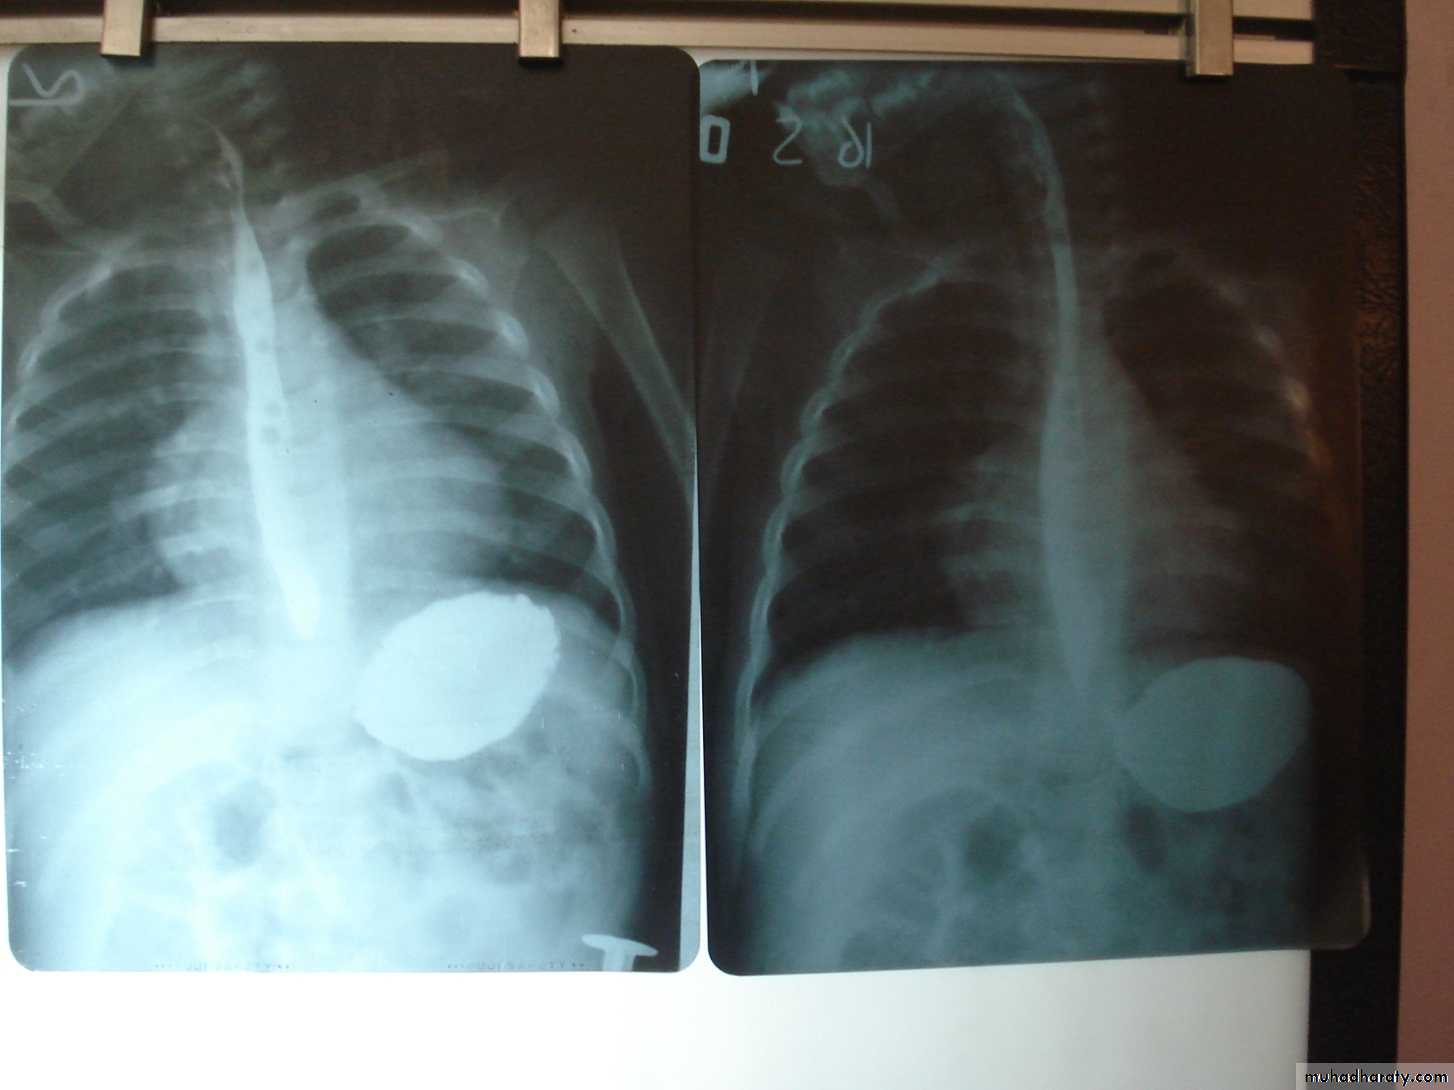

SLIDE NO. ((8))A. What abnormality you see in this X-ray?B. what is the diagnosis?

SLIDE NO.((9)) A.What is your diagnosisB. give two nonsurgical causes of acute abdomen